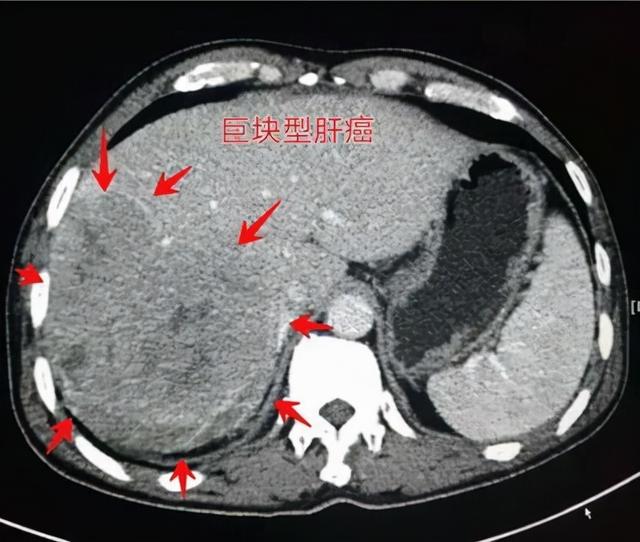

该患者后来没有再找过我,一晃五年半过去了,2020年10月因为腹胀、消瘦又到门诊来看病。彩超提示肝脏巨大占位(13厘米✖12厘米),胆囊和胰腺因为受压迫而移位。甲胎蛋白和异常凝血酶原都高达三位数,可以明确诊断是巨块型肝癌。乙肝表面抗原定量3.412 IU/ml(雅培试剂),HBVDNA定量<100拷贝/ml,高灵敏病毒量检测结果为2.54 E+02 IU/ml。

所谓的病毒量低于检测下限有时候是不靠谱的,尤其是小三阳或者小二阳肝炎。该患者应该是典型的小三阳肝炎,乙肝表面抗原定量个位数,很低,但是病毒复制是持续的,肝脏炎症和纤维化持续进展,再加上几十年的抽烟和重叠幽门螺杆菌感染等危险因素,又耽误了定期复查,最终发展成巨块型肝癌。